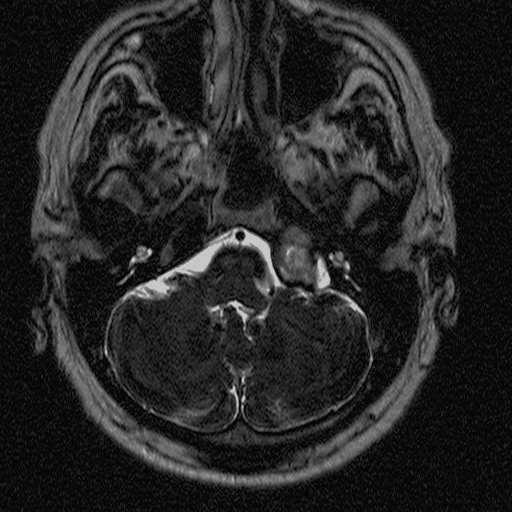

1. image: Patient with sensorineural hearing loss and tinnitus. MR-study (T2, precontrast T1 and postcontrast T1) reveal a mass in the left pontocerebellar angle without significant contrast enhancement. HRCT proves that the mass arises from the petrous pyramid, suggesting cholesterol granuloma. (Asklepios Klinik Altona, Hamburg)